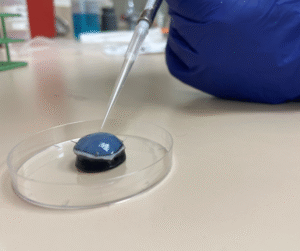

Treatment of the Petri plates inoculated with live bacteria using Ocu-Vet UV-C for 15 seconds at a 10 mm distance.

Treatment of the inoculated cornea with UV-C for 15 seconds at a distance of 10 mm.